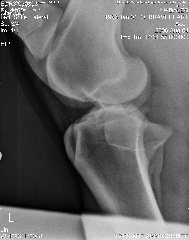

Here are the xrays from today:

Stifle oblique:

Stifle Oblique

Hi Dr. O, after reading your article, I've added the lateral view of the stifle, can you tell if you can see if he has any of the following?

osteochonDrOsis dissecans

subchondral bone cyst

osteoarthritis

Stifle Lateral view

stifle lateral

Aileen, carefully reviewing an extensive list of radiographs like you have above for any abnormality even with the original set of full sized radiographs could take up to an hour and an hour more to write about. Reviewing these tiny pictures would be of no value at all. While I don't mind looking at the occasional radiograph the above is beyond the scope of this site.

If you want a second opinion on these I strongly recommend you send them to a certified veterinary radiologist, like you find at a university veterinary school, they could tell you more than I would be able to.

Surgeon says mild to moderate djd in hocks and stifle. His stiffness is much much better, not overall anymore, so I do think the hock injections helped.